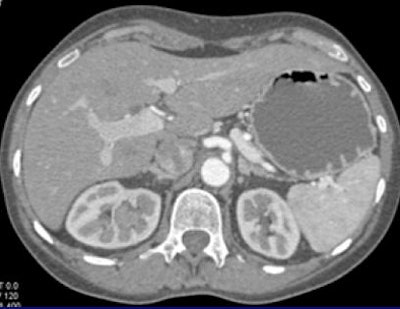

In one patient example, a small hypervascular lesion in the left kidney could not be seen in the early corticomedullary phase, even when the image was viewed in multiple planes, in volume rendering (VR) and maximum-intensity projections (MIPs). It became "a fairly obvious lesion on excretory-phase imaging," Fishman said.

![]() |

| Subtle renal cell carcinoma not visualized in any plane in the arterial phase (above) becomes fairly obvious in excretory-phase image (below). All images courtesy of Dr. Elliot Fishman. |